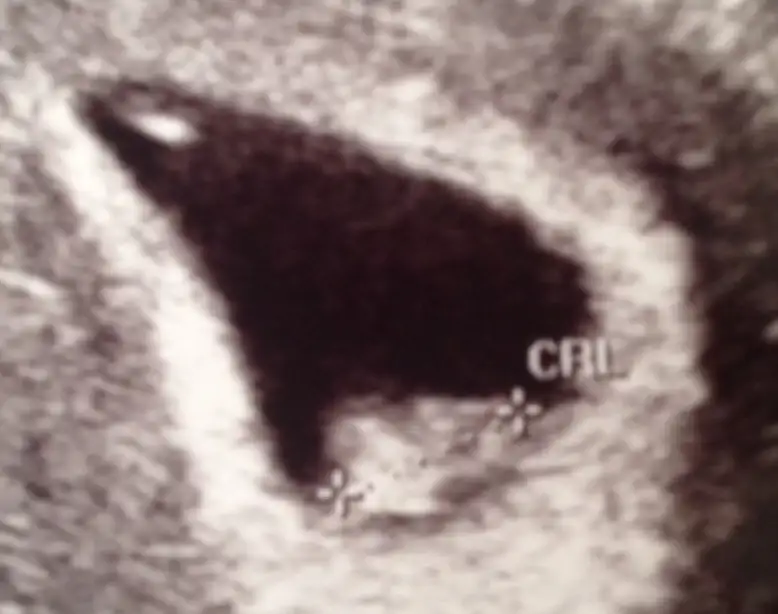

Günaydın kızlar şu benim garip kese şeklime bi yorum yapar mısınız? Armut şeklinde, üçgen gibi alt geniş kısmında bebek var. Annem çok normal diyor ama ne yuvarlak ne fasulye. Acaba kontrolde doktor bastırınca mı böyle garip şekil aldı bilmiyorum dr da olumsuz bişey demedi ama. Tecrübeli annişler bi görsün istedim

• image.webp

13,7 KB · Görüntüleme: 83

canım benım tek bıldıgım orantılı bı seklı olmadıgı herseferınde şeklı degıscek merak etme. ne guzel yatmıs kuzucuk oraya ohhhhhh çadır yapmıs kendıne :)

Canim normal sanirim kesen.. Doktorun aleti tutusuyla bile degisebiliyor.. Benim ayni gun cekilen iki goruntude kese sekilleri birbirinden farkli gorunuyor.. Bebisin kac mm olmus..

bu çarşamba gününün 7+2 iken 1 cm di haftasına göre normal dedi biz en çok kanamadan endişelendiğimiz için bebeğin gelişimiyle ilgili pek soru soramadım ama inşallah normaldir

Aynen canim benim de kanamam var bebis yasiyo diye cok mutlu olmustum.. Benim de 7+3de 1cmdi.. İnsallah iyilerdir..